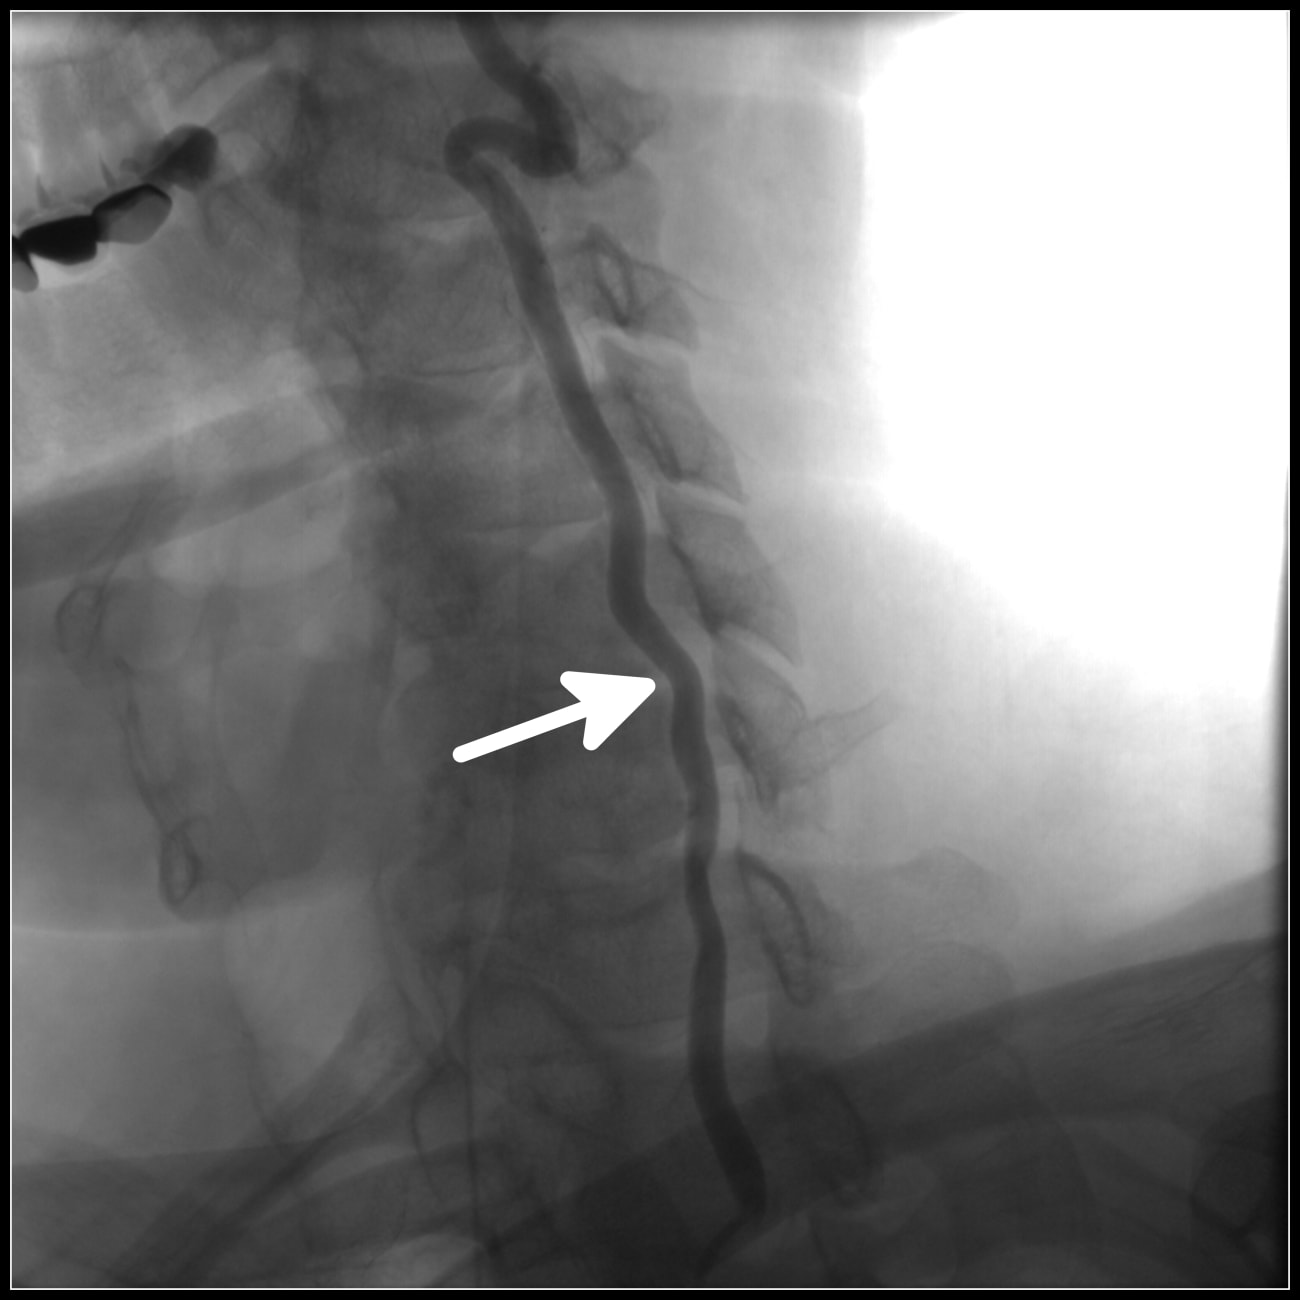

He referred her to the Johns Hopkins Transverse Myelitis Center, a hub for experts in the disease of transverse myelitis itself, but also for a variety of other conditions that affect the spinal cord. Under the guidance of McArthur’s colleagues Carlos Pardo-Villamizar and Phillipe Gailloud, Whitmore underwent a spinal angiogram, showing concretely that she’d undergone a spinal cord stroke — a rare manifestation of neurologic ischemia. The extreme infrequency of this condition, affecting only a few patients in the U.S. per year, and Whitmore’s unconventional presentation of gradual decline stymied her timely diagnosis, McArthur explains.